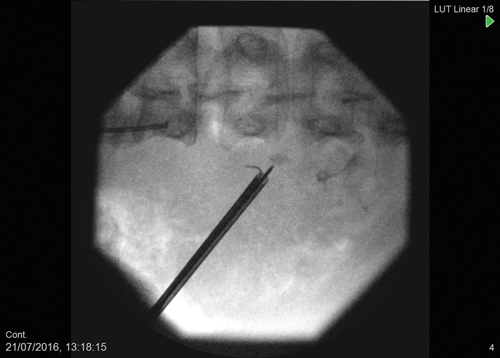

Figure 2: Intraoperative ultramini PCNL fluoroscopy showing type IV non-communicating

calyceal diverticular stone with puncture directly on to stone.

The 3.5Fr ultramini nephroscope is then passed into the diverticulum with saline irrigation (Figure 2). Blood clots from the percutaneous puncture can be removed using the vortex effect or using a tipless basket e.g. Zerotip™ (Boston Scientific, USA). Once the calculus has been identified a 200 micron laser fibre can then be inserted down the working channel of the nephroscope to fragment the calculus. Fragments can then be removed with either basket or vortex effect (Figure 3).